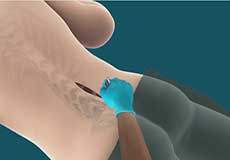

Epidural Steroid Injections

Epidural steroid injection (ESI) is a minimally invasive approach to treat inflammation of spinal nerves that causes pain in the neck, arms, back and legs. This technique may help relieve back pain in conditions such as spinal stenosis, spondylolysis or herniated discs. In this technique, the steroidal medications are injected into the spinal canal so as to pass down to the inflamed spinal nerve through the epidural space which lies between the covering of the spinal cord and the vertebrae. An ESI contains a corticosteroid medication along with an anesthetic agent which can reduce the inflammation and pain.